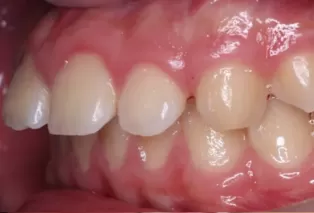

Photos intra-orales